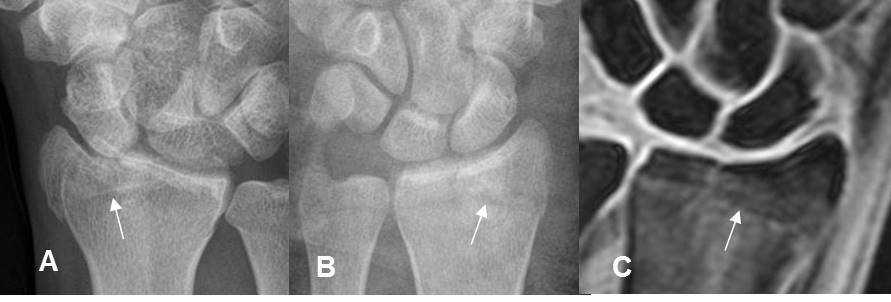

Fig 184. Fractura de Chauffeur.

A y B: Rx AP de muñeca. C: RM coronal en STIR. Fractura intra-articular y en sentido oblicuo, en la parte lateral del radio distal.